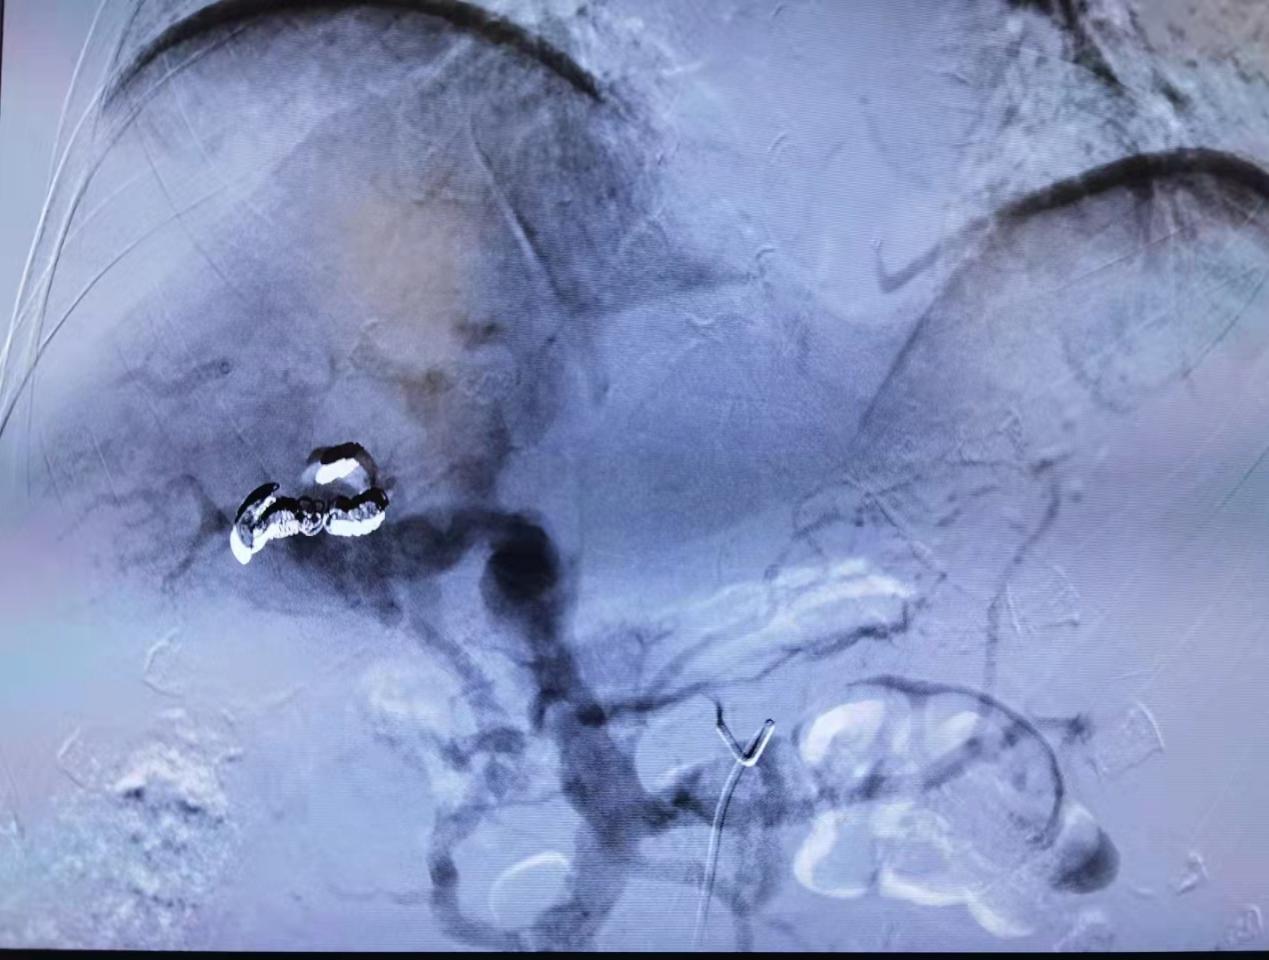

图一:肝动脉造影,见巨大明显肝动脉-门静脉瘘,及外院治疗时的弹簧圈;

图二:肝动脉造影,见门静脉明显显影(导致门脉高压)